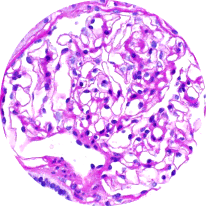

Light microscopy

Provides initial diagnostic evaluation, assessing patterns of glomerular injury. Does not distinguish between forms of glomerulonephritis2,21

Healthy glomeruli

MPGN pattern of injury

(C3G/IC-MPGN)